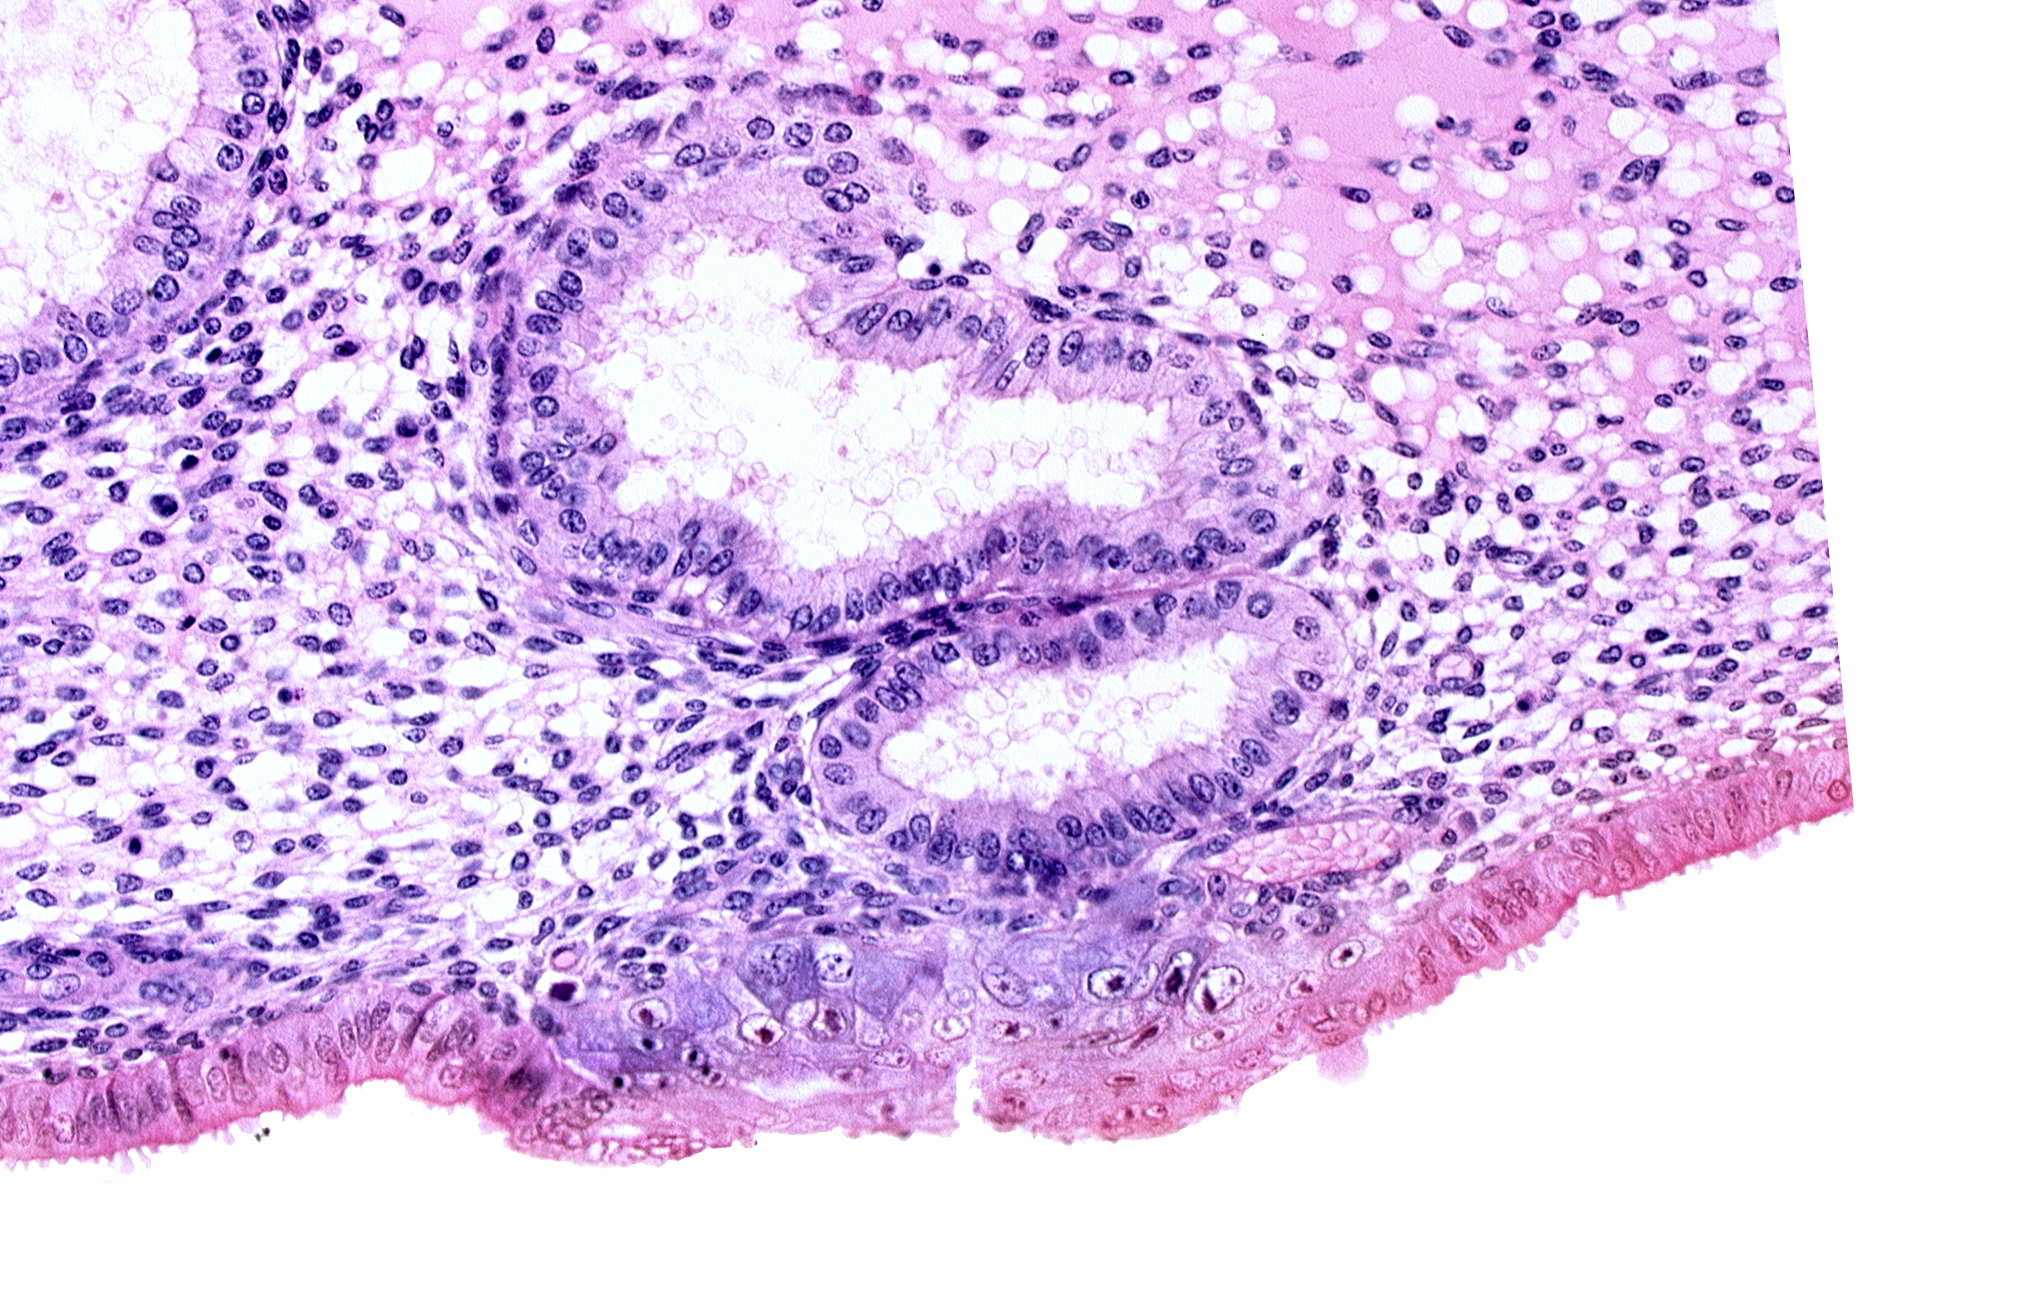

Carnegie Embryo #8020 | Location: 06-04-07

Keywords: cytotrophoblast, edematous endometrial stroma (decidua), edge of blastocystic cavity (blastocoele), endometrial epithelium, endometrial gland, solid syncytiotrophoblast, uterine cavity

Source: The Virtual Human Embryo.